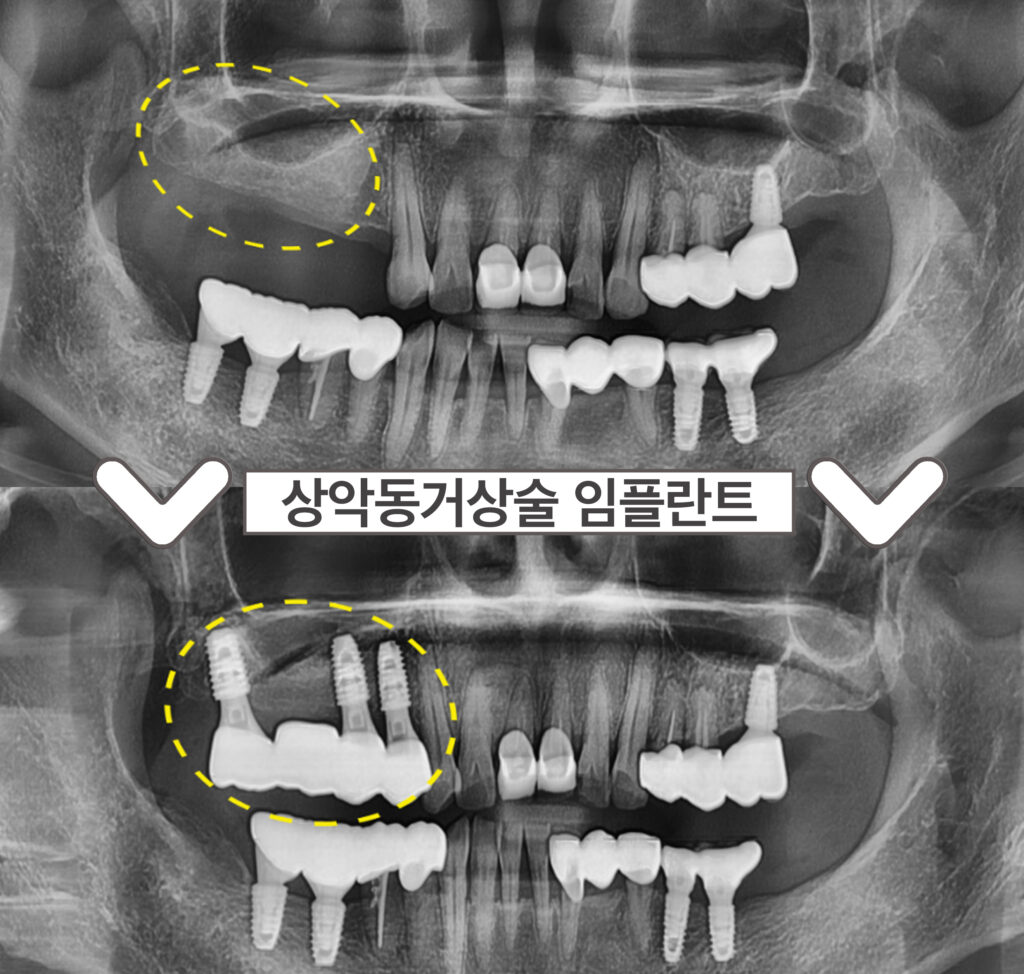

정밀한 검사를 위해

파노라마 사진을 촬영해 보았더니

위턱의 오른쪽 첫 번째 작은 어금니(#14)부터

두 번째 큰 어금니(#17)까지

모두 4개의 어금니가 상실된 상태였는데요.

부천시청역치과 서울이로운에서는

3D-CT 촬영을 통해

잇몸뼈의 상태를 꼼꼼하게 진.단 한 후

정밀한 검사를 진행한 결과

임플란트를 식립하기 좋은 위치를 선정하여

3개의 임플란트를 식립하고

4개의 보철물로 연결해 주는

브릿지 방법으로

치료계획을 수립하였습니다.

그리고 위턱 왼쪽 어금니 자리에

상악동막이 내려와 있어

잔존 뼈와 상악동까지의

수직적인 뼈의 양이 부족하여

상악동 거상술 중

치조정 접근법을 활용하여

임플란트 식립을 진행하기로 하였는데요.